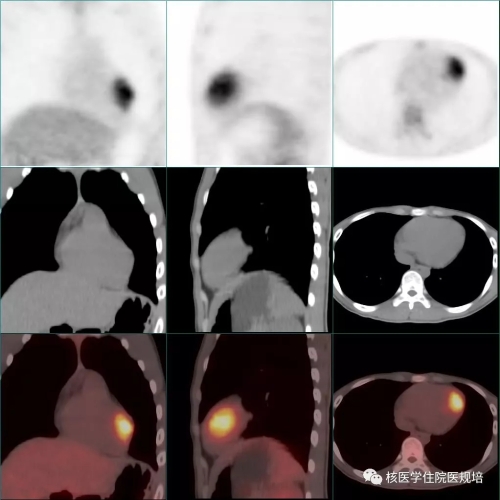

18F-FDG PET/CT显像见:左室前侧壁显影形态失常,MR所示占位相应部位与周围正常心肌组织对比呈不均匀FDG摄取减低区(SUVmax6.4),但肿物边界观察不清,相当于乳头肌处见点状FDG高摄取(图4);双侧腋窝区域分别可见一FDG摄取轻度增高(SUVmax1.8)的小淋巴结,对称性分布,淋巴结均呈长椭圆形,短径均小于1.0cm,内可见脂肪密度的门样结构(图5);另于左侧臀部下方皮下脂肪层内可见一点状FDG摄取增高灶(SUVmax6.1),相应部位CT见一边界较清晰的软组织密度结节影(图6,追问病史该结节已存在3年,局部无红肿热痛,大小始终无著变。全身其余部位未见明显异常结构改变及FDG摄取。

图4